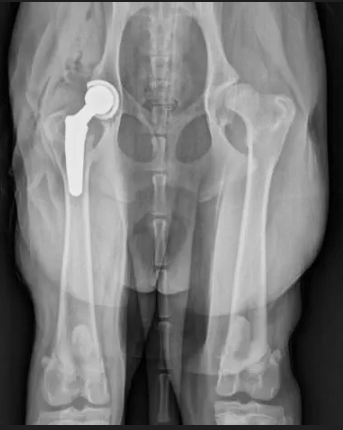

Esse é Bill Gates, 1 ano e 7 meses de idade. Atualmente já foram feitas duas cirurgias, uma ablação e uma remoção de tumor. Ele está com displasia coxofemoral bilateral subluxada e suspeita de sindrome da cauda equina..

Ele precisa passar por uma cirurgia chamada Artroplastia total do quadril, é uma cirurgia que substitui a articulação desgastada (cabeça do fêmur). Esse é um exemplo de uma prótese de quadril, o que ele mais precisa atualmente.